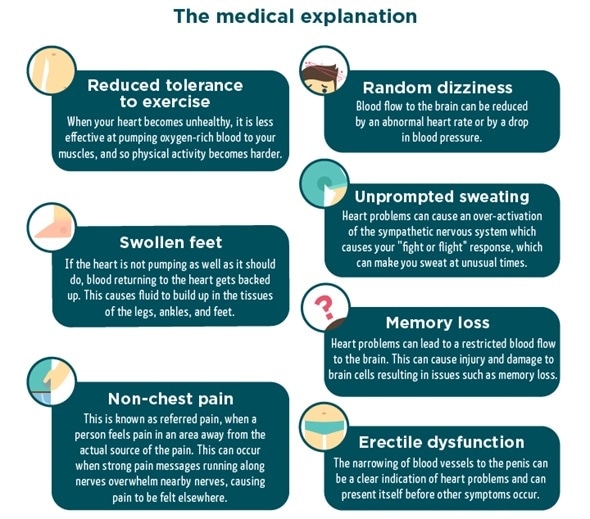

Swollen feet

A tightness in your shoes or visible swelling of your feet can indicate a heart problem. This can occur as a result of slowed circulation – as blood flows out of the heart at a slower rate, blood returning to the heart gets backed up. You may then witness a build-up in the tissues surrounding the feet, legs and ankles.

Erectile dysfunction

In men, erectile dysfunction (ED) can be a strong indicator of issues with your heart and circulatory system. It occurs when the tiny blood vessels feeding the penis don’t receive enough blood to maintain an erection sufficient for sex. ED can present itself far in advance of other symptoms, so it’s a good idea to watch out for it and act early.

Referred pain

Pain related to heart problems can occur in places other than the chest. You can experience ‘referred pain’, which occurs when pain messages running down nerves overwhelm nearby nerves. Referred pain linked to heart problems usually occurs in the shoulders, arms, jaw and neck.

Difficulty doing physical tasks

Struggling to execute simple physical tasks is a clear sign of a struggling circulatory system. You may find yourself short of breath when climbing the stairs, or feel a need to rest more often than in the past when exercising. This can indicate a reduction in your heart’s ability to supply your muscles with an oxygen-rich flow of blood.

Memory loss

Confusion and muddled thinking may indicate that your brain is not receiving a sufficient amount of blood. If left unaddressed, this can seriously damage your brain cells and lead to memory loss.